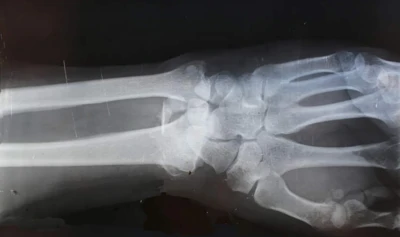

Inventatorii Bone-02 au prezentat un caz experimental al unui pacient cu o fractură la încheietura mâinii, care a primit o injecție printr-o incizie de doar 3 cm și s-a vindecat în doar trei minute. Operația de reparare a încheieturii mâinii ar fi necesitat o placă metalică și șuruburi, a căror îndepărtare ar fi necesitat o a doua operație în anul următor.

După o consultație de control la trei luni, fractura pacientului se vindecase complet, fără complicații. Acesta a fost doar unul dintre cel puțin 150 de cazuri documentate în care Bone-02 a fost utilizat cu succes pentru tratarea fracturilor.